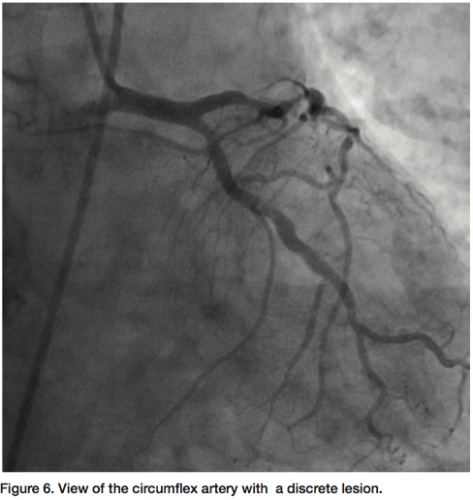

be totally occluded (probably chronic) (Figure 5) and a large posterior descending artery (PDA)/postero-lateral artery (PLA) system is noticed on angiography of the left arteries. The collaterals to the PDA/PLA appear to come from the left anterior descending coronary artery (LAD) and circumflex (Figure 6). The chronic total occlusion (CTO) appears moderate in length once the collateral and main vessels are visualized, with a calcific channel outlined.

The LAD shows “lumpidy-bumps,” but nothing more than a 70-80% (remember, it is subjective) lesion (Figure 7). There are smaller lesions throughout the artery. The circumflex has a lesion that could be repaired with angioplasty (Figure 8).